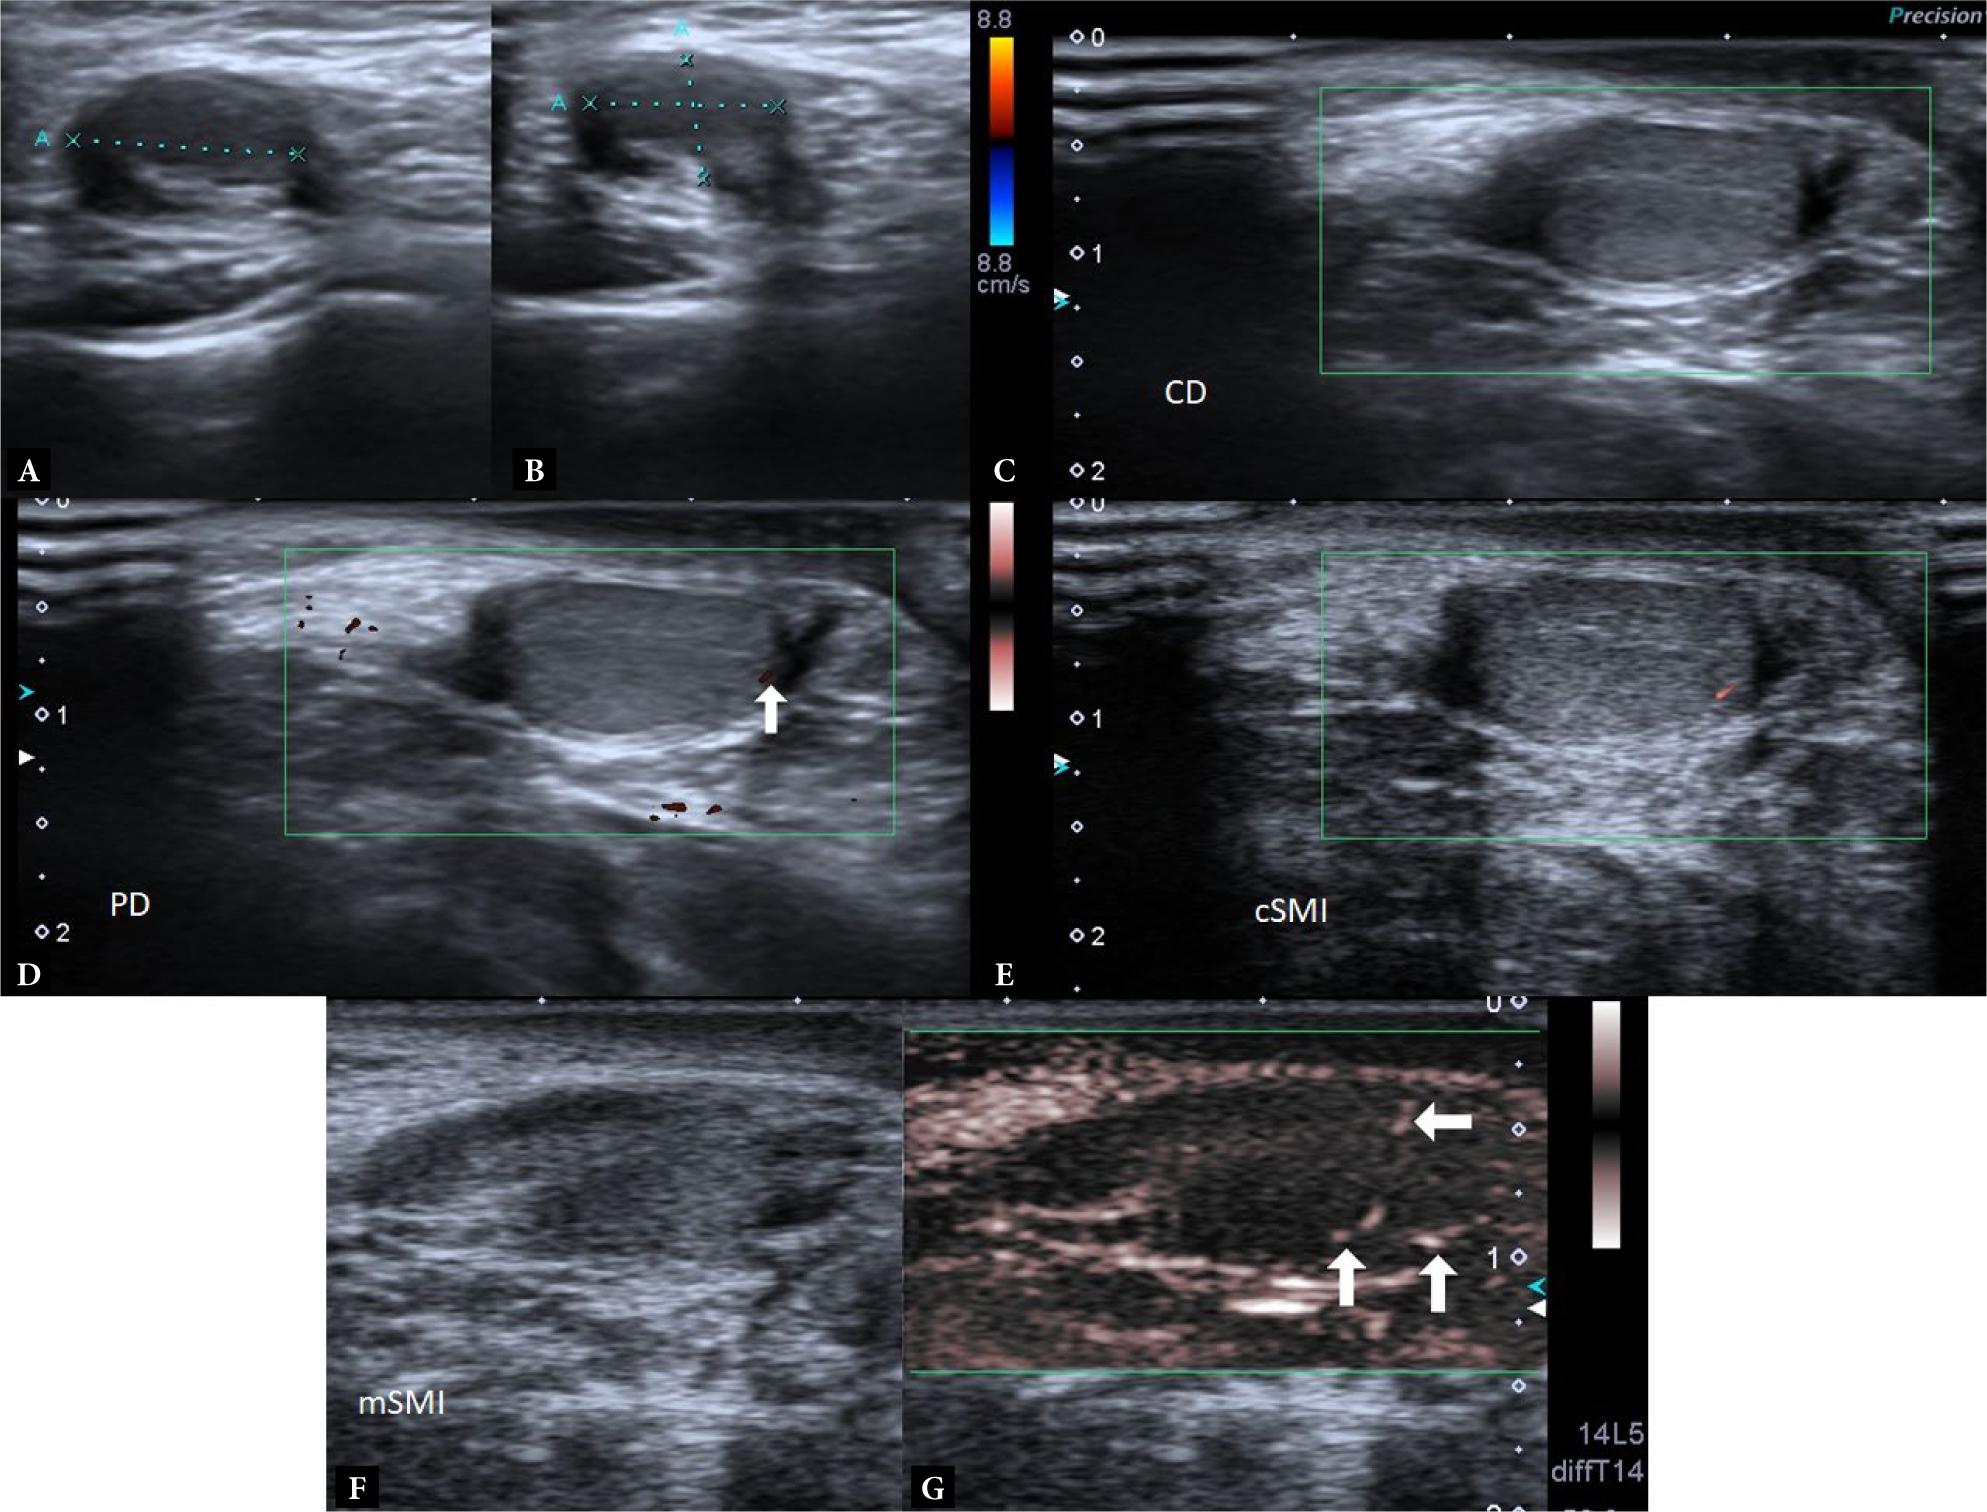

Fig. 1.

Testes of operated 44 patients (OUT, testes having contralateral inguinal canal distal placement under follow-up and contralateral normally located testes) in terms of age, volume, and SCE-LFCE numerical values_ (SCE: spot color encoding, LFCE: linear flow color encoding, CD: color Doppler, PD: power Doppler)